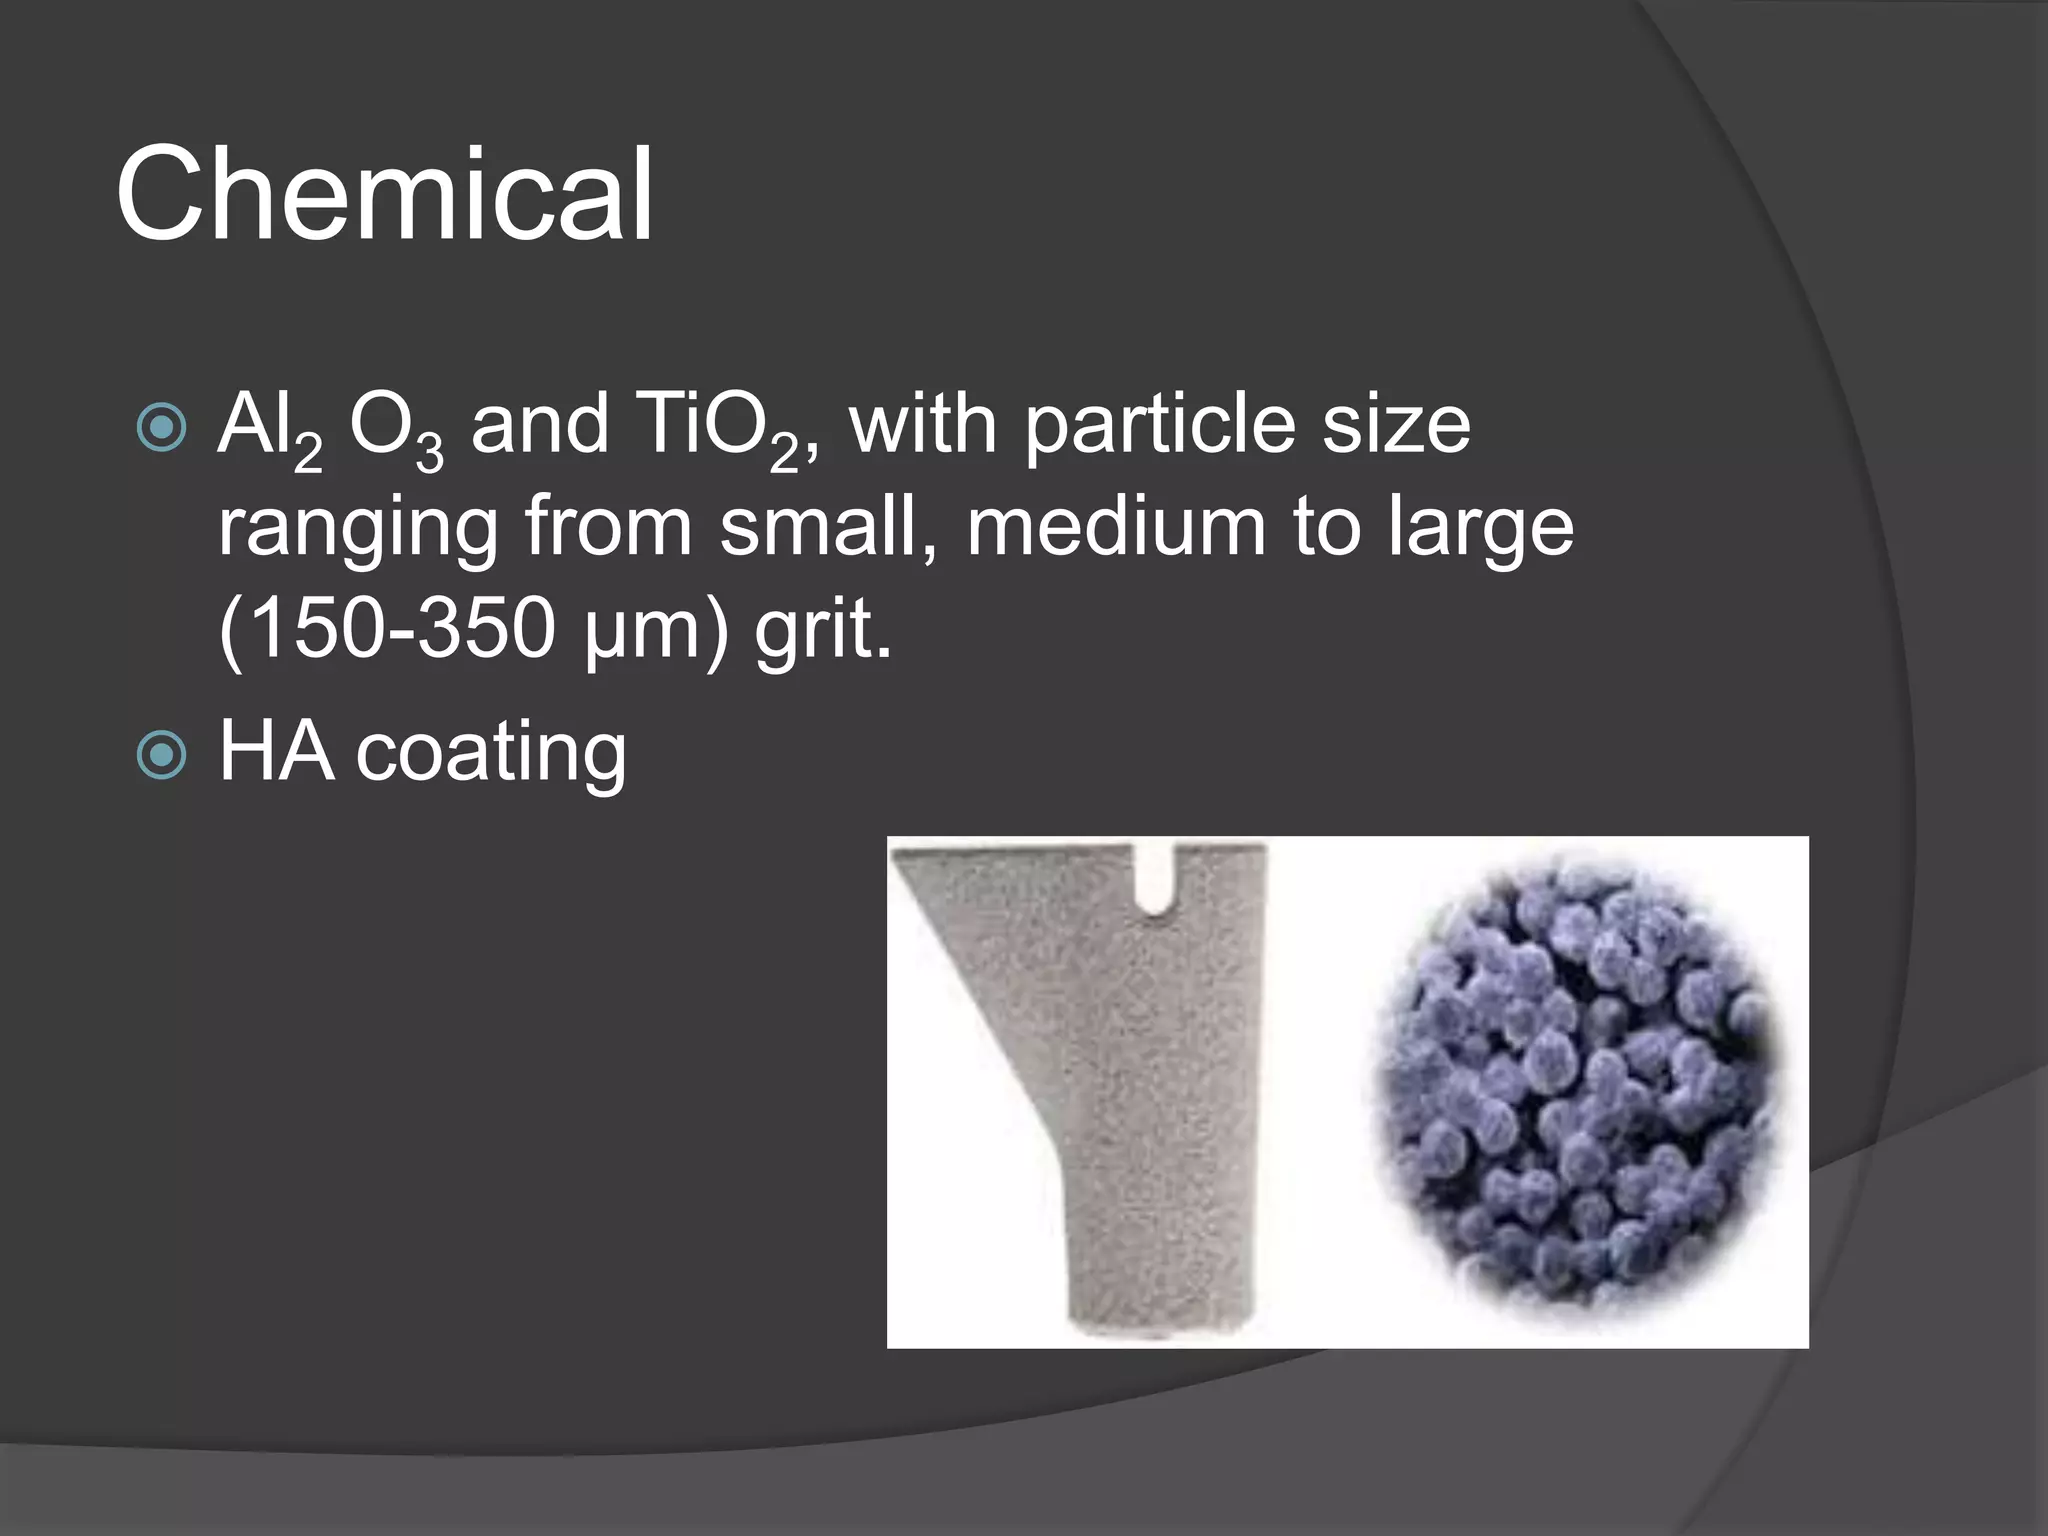

This document discusses factors that influence osseointegration and primary stability of dental implants, including implant design characteristics, surgical technique, and loading protocols. Specifically, it covers the processes of osseointegration and how forces on implants can either promote or inhibit bone remodeling. Key implant design considerations like length, diameter, threads, coatings and surface topography are analyzed in terms of their effects on stress distribution and bone-implant contact. The importance of primary stability and factors influencing it like bone quality and surgical skill are also addressed. Loading protocols ranging from immediate to conventional loading are compared.